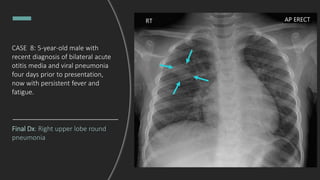

CASE 8: 5-year-old male with

recent diagnosis of bilateral acute

otitis media and viral pneumonia

four days prior to presentation,

now with persistent fever and

fatigue.

What do you see?

Final Dx: Right upper lobe round

pneumonia

CASE 9: 3-year-old female